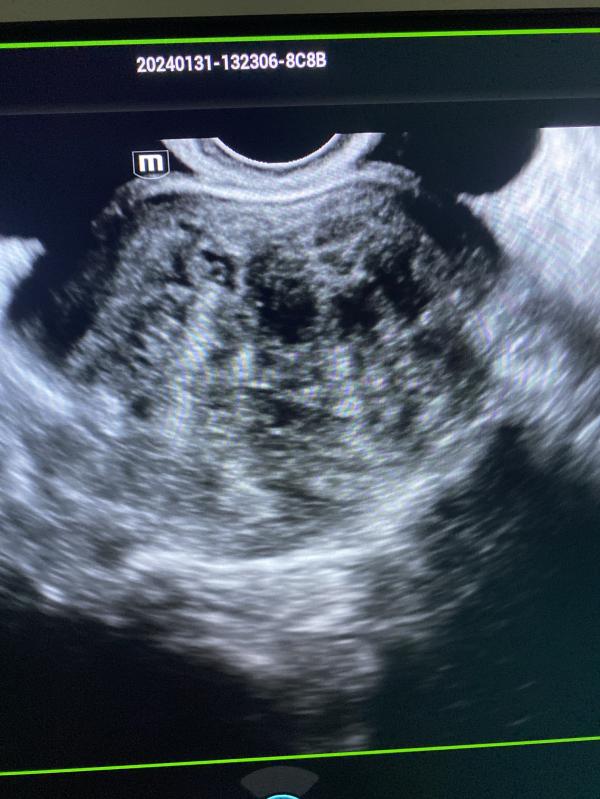

Узи миома матки: можно ли увидеть миому на снимке УЗИ? Случаи миомы и камней в почках

Можете на узи снимке увидеть миому матки?

Сегодня было много миом .

Вчера день был богат на камни в почках.